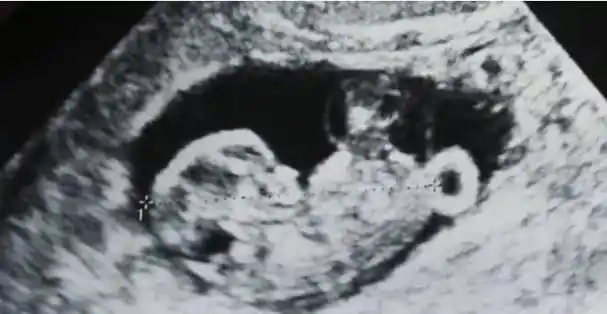

"照片中可以很明显的看见胎儿可爱的小脚丫.

大s晒二胎儿子b超似点赞 称结婚五年不易